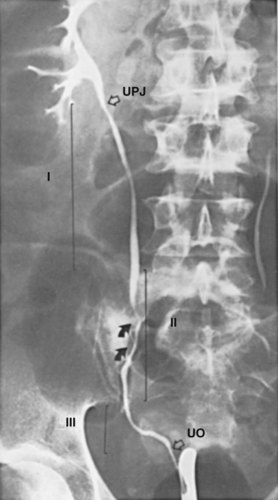

The normal ureter is not of uniform caliber, with three distinct narrowings classically described: the ureteropelvic junction, crossing of the iliac vessels, and the ureterovesical junction (Fig. 1–45). At the ureteropelvic junction, the renal pelvis tapers into the proximal ureter. In many cases, this perceived narrowing may be more apparent than real, with no evidence of obstruction evident on radiographic or endoscopic investigation. The second region of narrowing occurs as the ureter crosses the iliac vessels. This is due to a combination of extrinsic compression of the ureter by the iliac vessels and the necessary anterior angulation of the ureter as it crosses the iliac vessels to enter into the pelvis. There is also no intrinsic change in the ureteral caliber at this location. The third site of narrowing observed in the normal ureter is the ureterovesical junction. There is a true physical restriction of the ureter as it makes the intramural passage through the bladder wall to the ureteral orifice. These three sites of ureteral narrowing are clinically significant because they are common locations for urinary calculi to lodge during passage. In addition, the angulation of the ureter, first anteriorly as it passes over the iliac vessels, then posteromedially as it enters the pelvis and courses behind the bladder, may restrict successful passage of rigid endoscopes. Appreciation of this normal angulation and the three-dimensional course of the ureter is critical for safe and successful ureteral endoscopy.

The ureter is often arbitrarily divided into segments to assist ureteral description. The simplest system divides the ureter into the abdominal ureter extending from renal pelvis to the iliac vessels and the pelvic ureter extending from the iliac vessels to the bladder. Alternatively, the ureter can be divided into upper, middle, and lower segments (Fig. 1–46). The upper ureter extends from the renal pelvis to the upper border of the sacrum. The middle ureter comprises the segment from the upper to the lower border of the sacrum. The lower (distal or pelvic) ureter extends from the lower border of the sacrum to the bladder.

Figure 1–46 The right ureter, illustrated by retrograde injection of contrast material. UO, ureteral orifice in the bladder; UPJ, ureteropelvic junction; I, upper ureter, extending to the upper border of the sacrum; II, middle ureter, extending to the lower border of the sacrum; III, distal or lower ureter, traversing the pelvis to end in the bladder. Arrows indicate the course of the common iliac artery and vein.